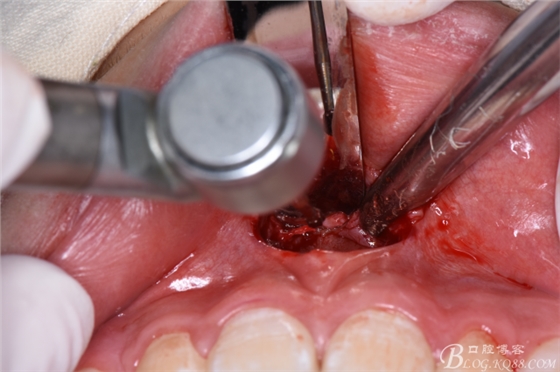

圖9.翻瓣、暴露唇側(cè)骨面,高速渦輪機(jī)去骨。

圖10.暴露出11、21之間的倒置多生牙牙冠